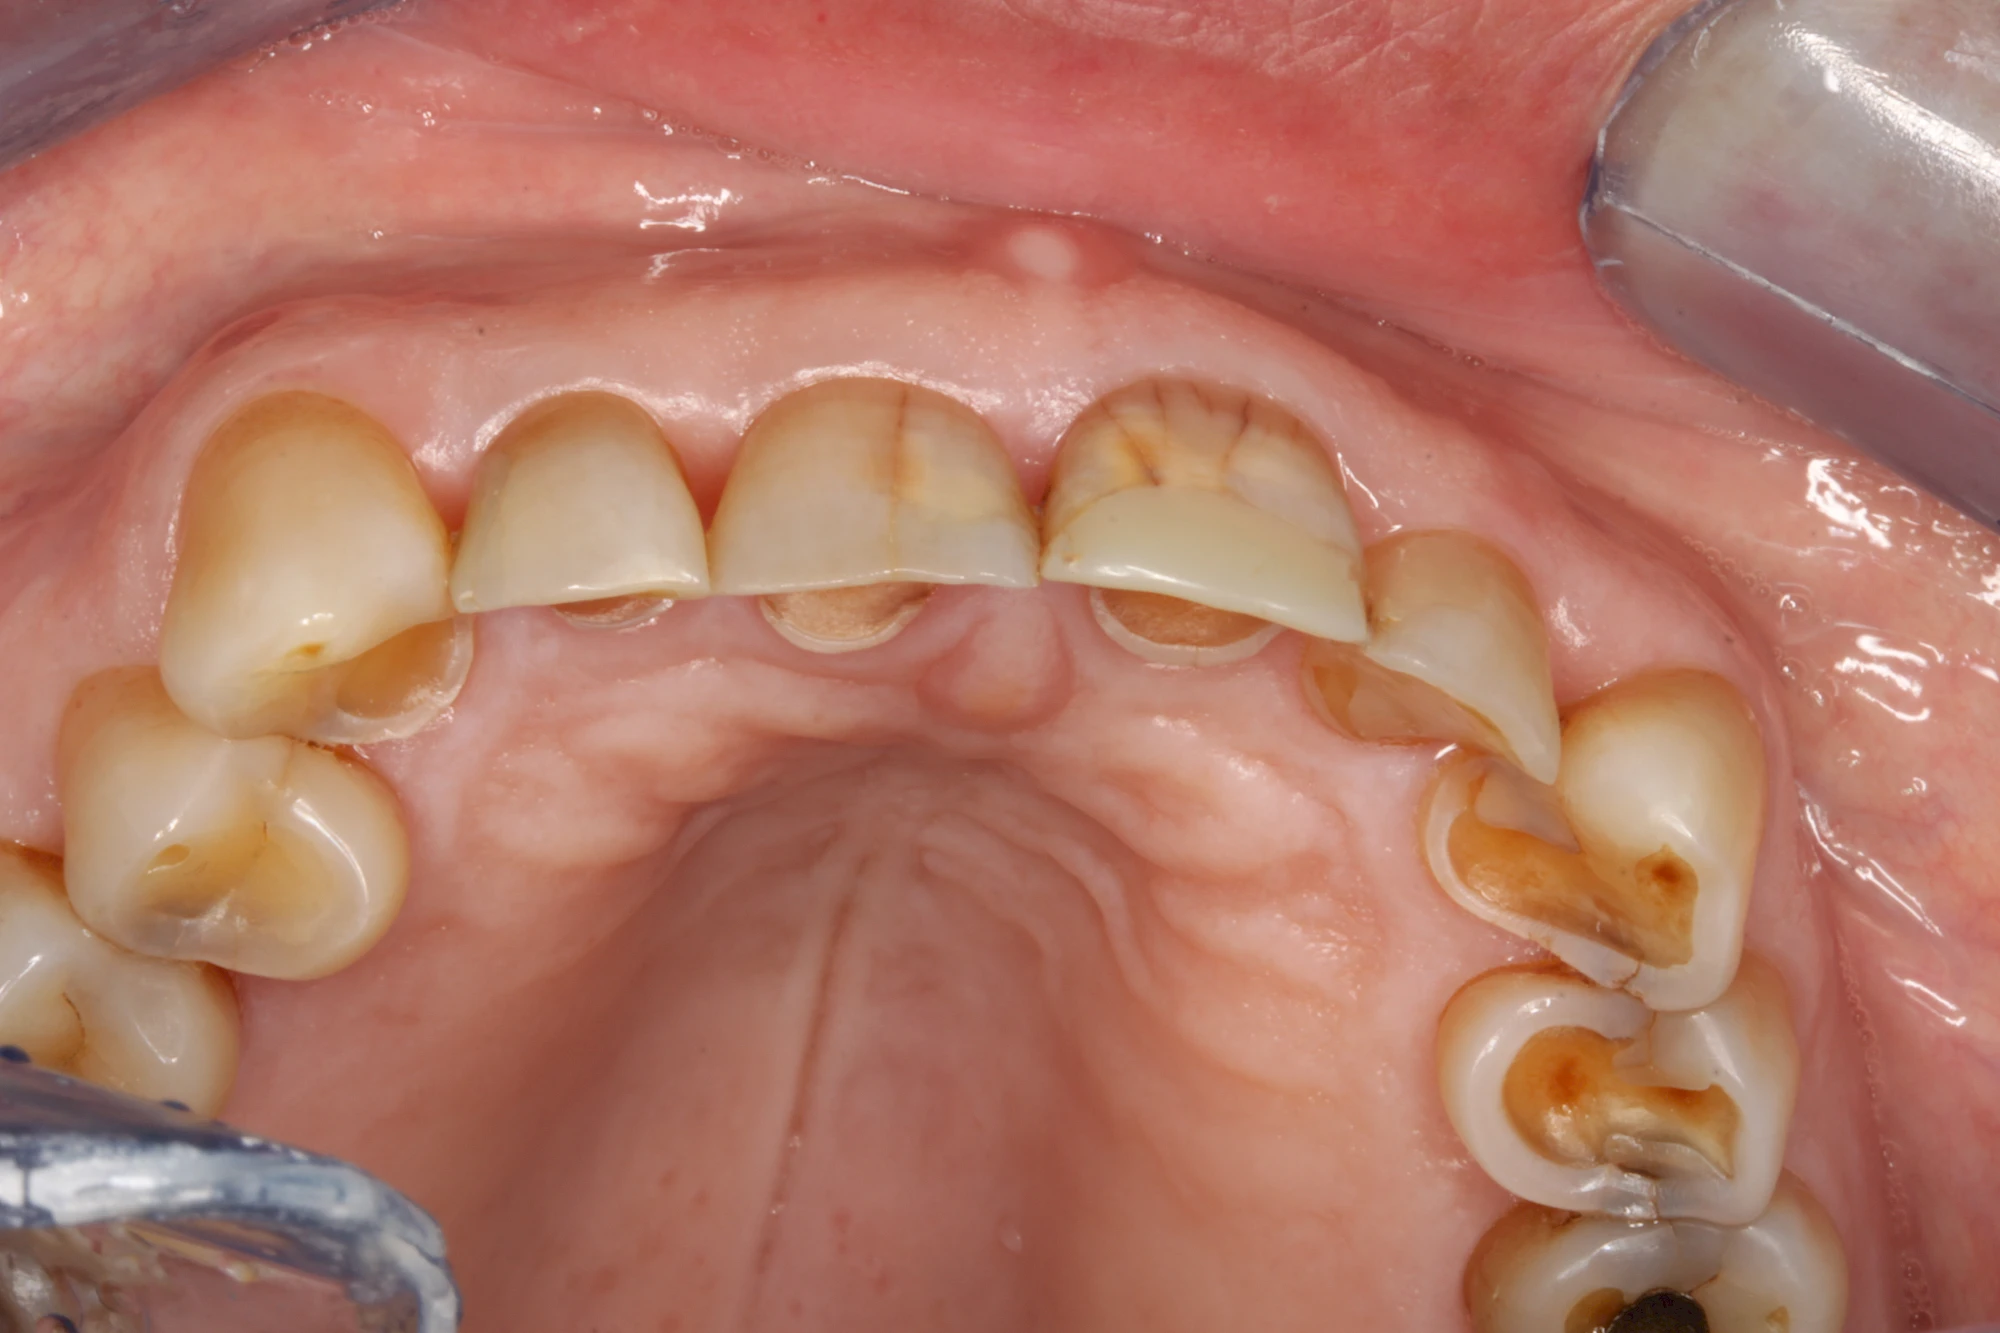

Auswaschung (Erosion) dagegen ist eine Verschleißerscheinung der Zähne aufgrund von immer wiederkehrenden Säureangriffen durch die Nahrung, verstärkt zum Beispiel durch den Genuss säurehaltiger Getränke oder Speisen. Auch bei Menschen mit einer Essstörung (z. B. Bulimie) können die Zähne durch die Magensäure ausgewaschen erscheinen.